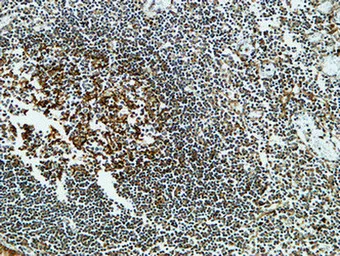

MPO Rabbit Polyclonal Antibody

Cat: APRab14056

Size1:50μl Price1:$118

Size2:100μl Price2:$220

Size3:500μl Price3:$980